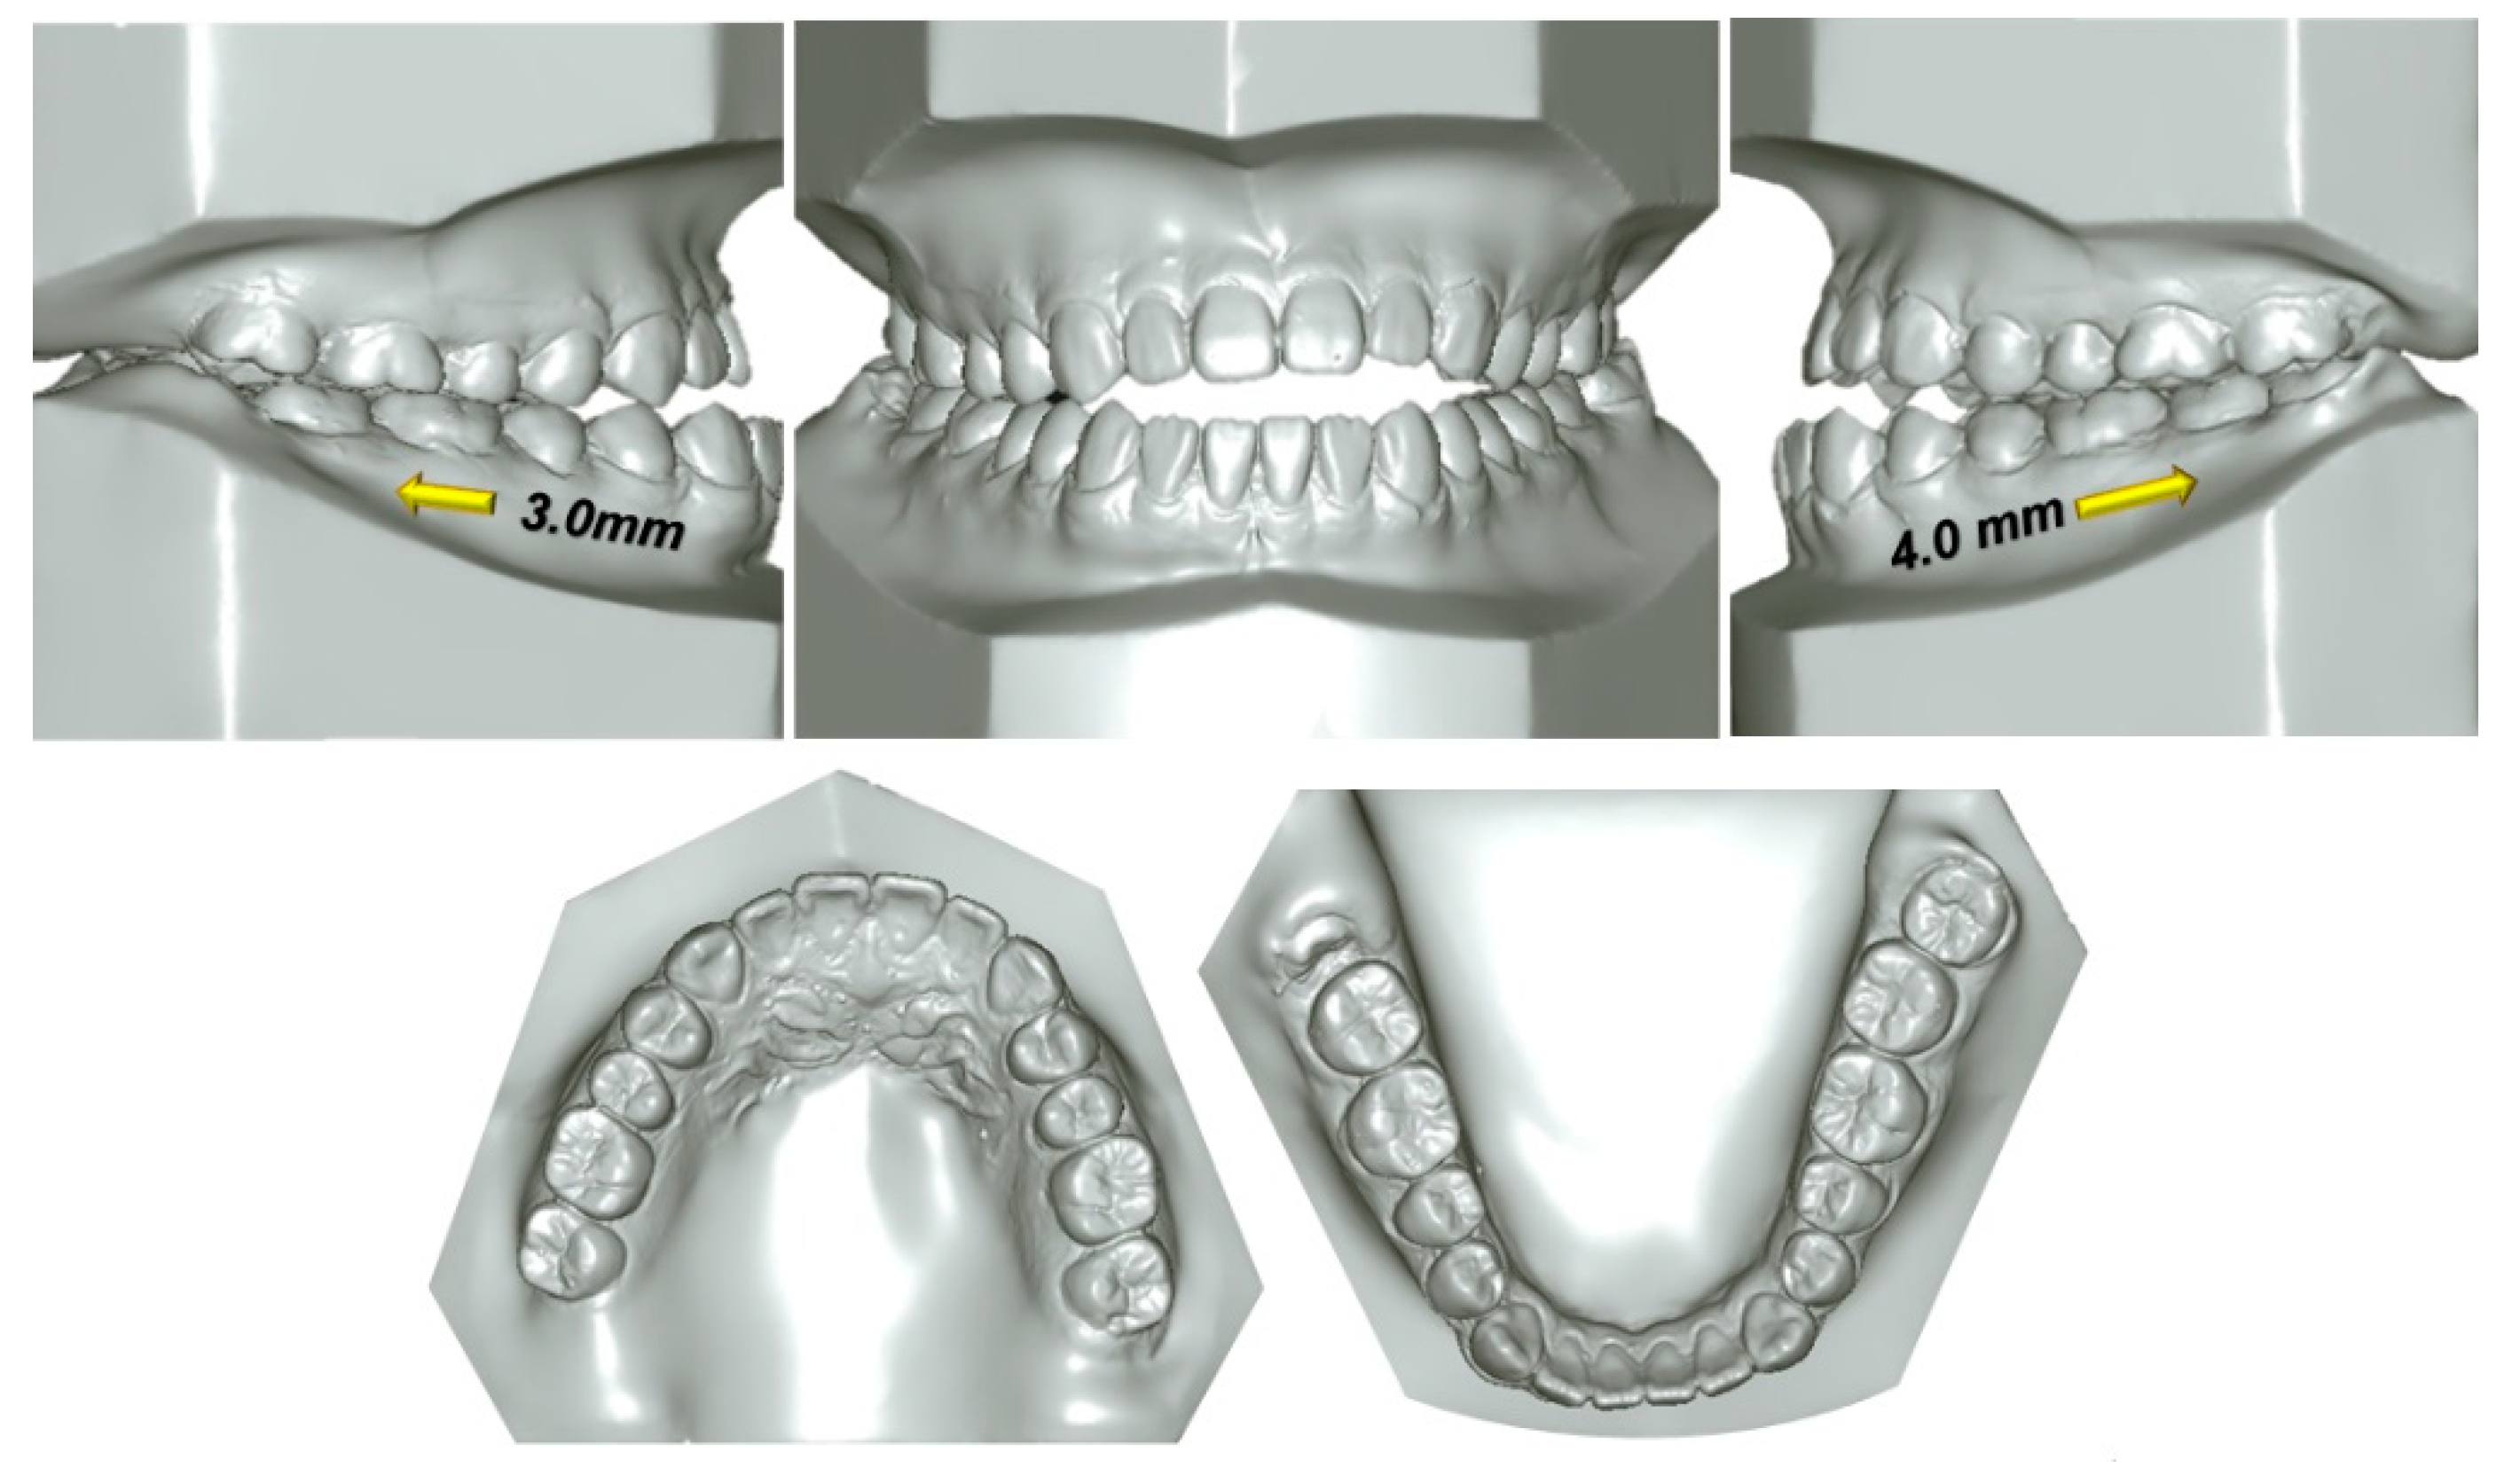

2. Case Report

2.1. Diagnosis and Etiology